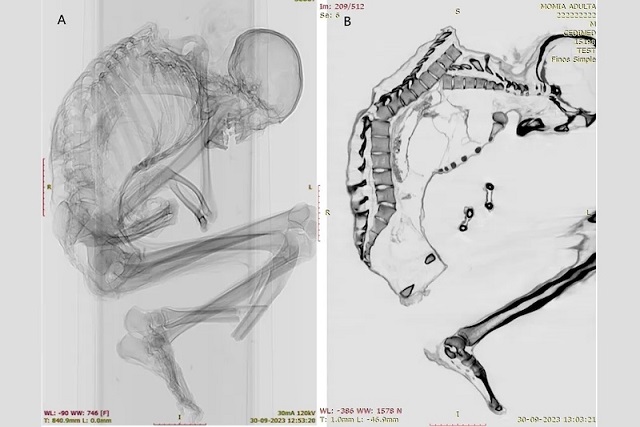

Mumyalaşmış madencinin bilgisayar tomografisi taraması, sırtında, kaburgalarında, köprücük kemiklerinde, kürek kemiklerinde ve alt ekstremite kemiklerinde travmatik yaralanmalar olduğunu ortaya çıkardı. C: Francisco Garrido ve Catalina Morales

International Journal of Osteoarchaeology dergisinde yayımlanan çalışmada, Şili’nin Santiago kentindeki Ulusal Doğa Tarihi Müzesi’nde görev yapan arkeologlar Catalina Morales ve Francisco Garrido, erkeğin ölümüne yol açmış olması muhtemel ağır travmanın ayrıntılarını ortaya çıkarmak için BT taramaları ve röntgen görüntülemeleri kullandı.

Mumyanın kemiklerinin yandan görünümü, omurgasının ciddi şekilde yerinden çıktığını ve alt bacağında kırık olduğunu gösteriyor. C: Francisco Garrido ve Catalina Morales

Erkeğin üst omurgasında iyileşmemiş çok sayıda kırık tespit edildi. Ayrıca kaburga, kürek kemiği ve köprücük kemiği kırıkları da vardı. Bunlar, araştırmacıların çalışmada yazdığına göre, sırtın üst kısmında “geniş bir alana yayılan künt kuvvetli bir darbeyi” düşündürüyor ve “üst sol göğüs kafesinin darbenin asıl yükünü taşıdığını” ortaya koyuyordu. Darbe, omurların bir kısmını yerinden oynatmış ve göğüs kafesinin çökmesine neden olmuştu.

Bunun yanı sıra, omurganın tabanına yakın bir omurda da kırık belirlendi; bu kırık muhtemelen üst sırt yaralanmasının dolaylı sonucu olarak oluşmuştu. Araştırmacılar, üst ve alt omurga yaralanmalarının her ikisinin de “genellikle ağır omurilik hasarı ve yüksek ölüm oranıyla ilişkili” olduğunu söylüyor.